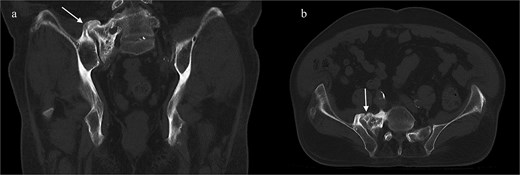

Next, a minimally invasive right SI joint bolt was placed. A second, 1-in. incision was made over the right lateral iliac fossa. A navigated drill was used to cannulate a pilot hole through the right ilium, crossing the sacroiliac joint, into the right sacral ala. A 12 mm tap was then used, and a 12 mm diameter, 50 mm length Rialto SI joint fusion implant was inserted across the right sacroiliac joint. A final O-arm scan was performed to confirm good position of all implants (Fig. 3).

Intraoperative O-arm spin confirmed placement of the right L4 and L5 pedicle screws, as well as the right iliac screw and right sacroiliac implant. The left-sided navigation clamp can be visualized. The patient’s spinal cord stimulator (seen in the figure) was carefully avoided. One can also see the pronounced osseous abnormality along the right lower spine, extending to the sacrum and medial ilium.